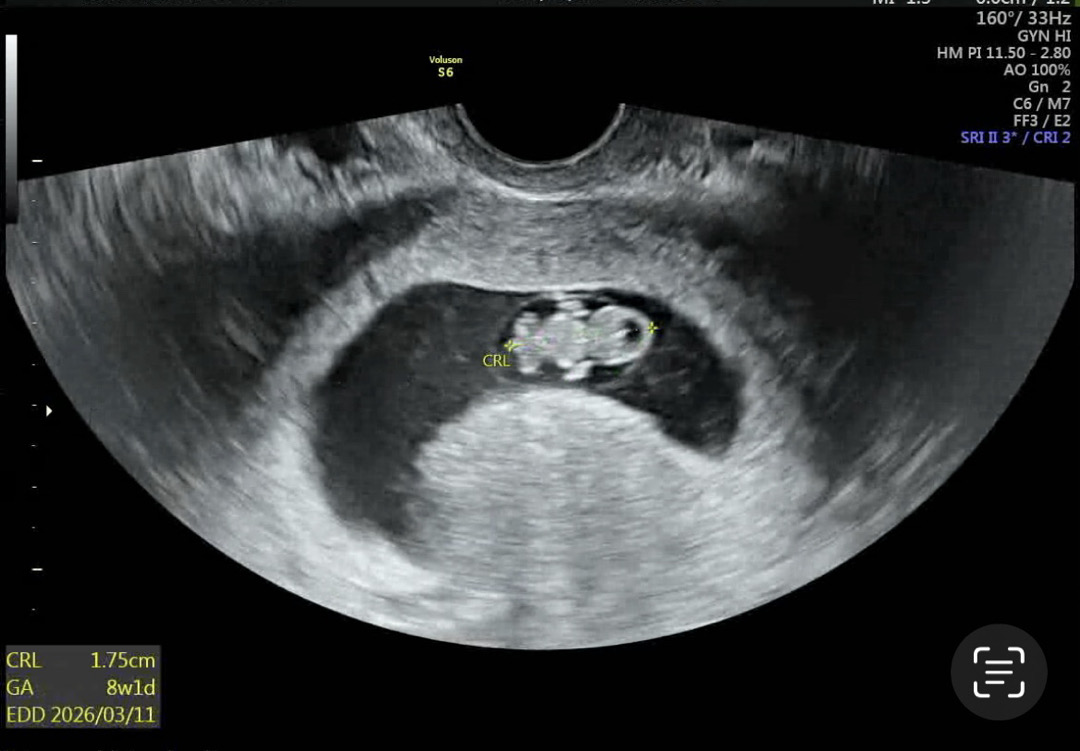

8주차 젤리곰 보구왓어용✨

엄청 쪼꾸만데 잇을거 다생긴 젤리곰 ㅠ 감동 100프로 너무 기엽쟈냐욤 ㅠㅠㅠ💛💛 4주뒤에 1차 기형아 검사 하러 오라시던데 니프티얘기는 없으셔서 혹시 1차 하면서 니프티 하신분 계신가욤 .. 아니면 1차 결과 보고 니프티 하는게 조을까욤 조언부탁드립니다👼🏻